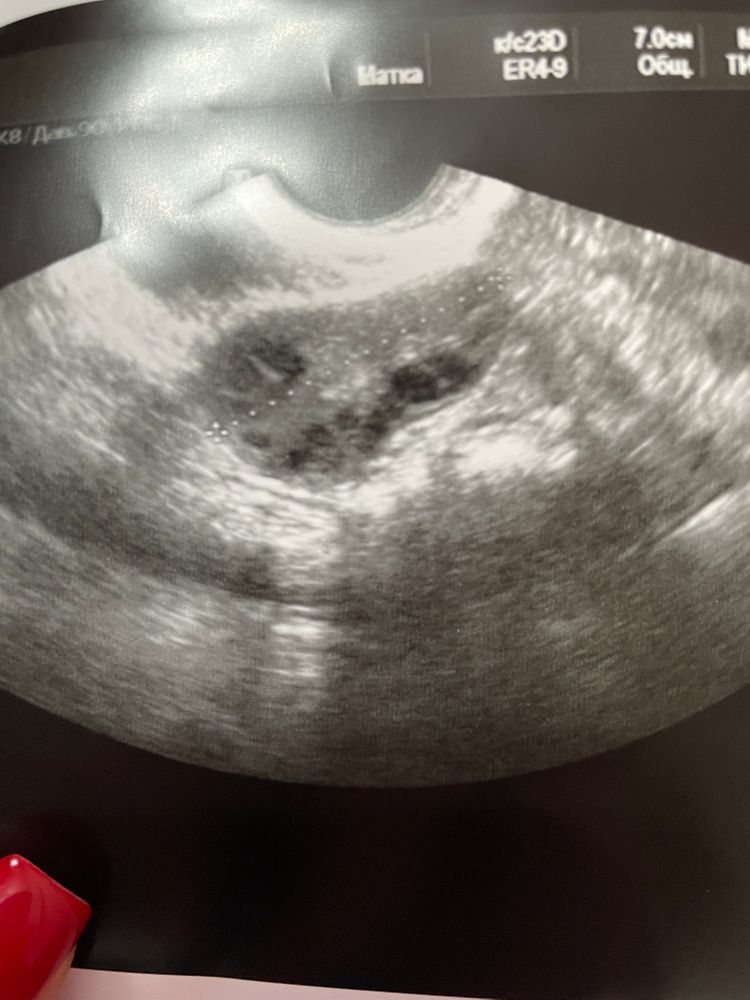

Девочки подскажите ,больше на целый фолликул или жт похоже ?